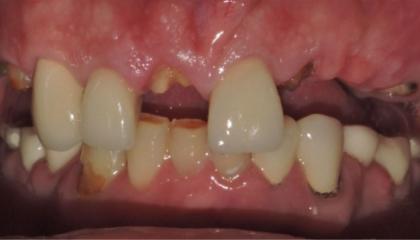

Before

Tooth Replacement

Zirconia bridge on Southern DC Implants